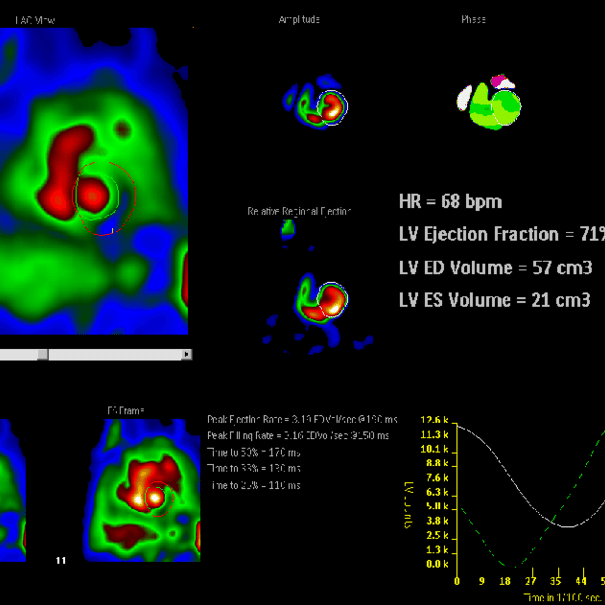

La cámara gamma detecta las emisiones de energía de la radiosonda en su cuerpo y las convierte en una imágen. La cámara gamma de por sí no emite ninguna radiación. Tiene detectores de radiación denominados cabezas de cámara gamma.